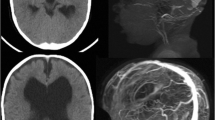

As shown in Fig. 2, the presence of right-sided hemoventricle detected at CT was clearly visible at TCS in patient 1. Similarly, the course of catheter was also visible at TCS (Fig. 3). Among the other qualitative parameters, the falx and the choroidal plexus, posterior cranial fossa, and brainstem were clearly visible in all patients (Fig. 4).

Postshunt evaluation at transcranial ultrasound (b, c) in comparison with CT (a, d). The course of catheter is clearly visible with transcranial ultrasound; ventricular size can be easily measured and monitored over time with bedside assessments. cCP, calcified choroid plexus, clPT, contralateral parietal teca, CP, cranioplasty, CT, computed tomography, HV, hemoventricle, IIIV, third ventricle, iVA, intraventricular adherences, lOH, left occipital horn, rFH, right frontal horn, SP, septum pellucidum, uV, upper vermis

Exemplificative picture showing the possibility to study the whole intracranial anatomy through fronto-temporo-parietal PEEK cranioplasty. Upper row: the TCS probe is placed in a “coronal” projection; bran parenchyma, lateral ventricles, third ventricle, interhemispheric fissure, tentorium, mesencephalon and brainstem are clearly visible and easily recognizable (a similar anatomic projection in on the right as reference). Lower row: through the fronto-temporo-pariental window, posterior cranial fossa anatomy can be easily studied; Doppler and color-doppler tools can, indeed, be used to assess perfusion. BS, brainstem, CV, cerebellar vermis, PCA, posterior cerebral artery, PEEK, polyetheretherketone, TCS, transcranial sonography